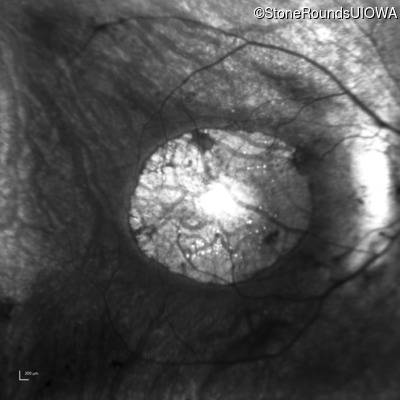

Age at visit: 16 years

This 15 year old male had a macular abnormality noted two weeks ago when he was refracted for his first pair of glasses. Bone spicule-like pigmentation was first noticed a year later (age 16) during a routine follow-up eye exam.